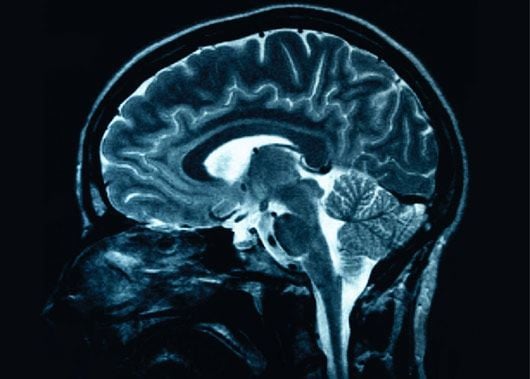

Rohanó életünk velejárója, hogy néhány apróság gyakran kimegy a fejünkből. Ez még nem jelent feltétlenül betegséget. Táplálkozással és egy kis odafigyeléssel elejét vehetjük memóriánk kisebb – nagyobb kihagyásainak és jobban kézben tarthatjuk életünket.Rendszeres testmozgással és a vércukor szinten tartásával már nagyon sokat tettünk agyunk megfelelő vérellátásáért.Szakítsunk időt minden nap az egészséges és kiadós reggelire. Ezzel beindul a vérkeringés és szervezetünk megfelelő anyagcseréje.Bizonyos tápanyagok kifejezetten az agyműködésre hatnak, ilyen legfontosabb a vas, mely elősegíti a vérben az oxigénellátást. Vasban gazdag táplálékok a húsok, elsősorban a vörös húsok, a máj, a búzacsíra, a sárgabarack, a hüvelyesek.B – vitamin forrásuk miatt érdemes minél több húst, szárnyast, májat, tejet, tojást és főzeléket fogyasztani. A hal, az avokádó, a dió esszenciális zsírsavakkal látják el szervezetünket, mely idegsejtjeink megfelelő működéséhez járul hozzá.A napi megfelelő folyadékfogyasztás természetesen elengedhetetlen.A koffein kizárólag rövid távon segíti a gondolkodást és túl nagy mennyiségben történő fogyasztása akár káros is lehet. A dohányzásról való leszokással sokat tehetünk a megfelelő vérellátásért.A stressz és a feszültség rontják a gondolkodást, a memória állapotát. Érdemes néha megállni rohanó világunkban és foglalkozni a bennünk lezajló folyamatokkal. A meditáció, a jóga mind pozitív hatással van lelki állapotunkra és ezáltal gondolataink tisztaságára.Életvitelünk átalakítása és tudatos szervezése, a teendőink feljegyzése előre vihet azon az úton, amit kitűztünk magunk elé.Az eltűnt használati tárgyak problémáját megelőzhetjük, ha rendet tartunk lakásunkban és mindent a helyére teszünk. Rendezett lakótér és környezet hozzájárul belső nyugalmunkhoz és tisztánlátásunkhoz.